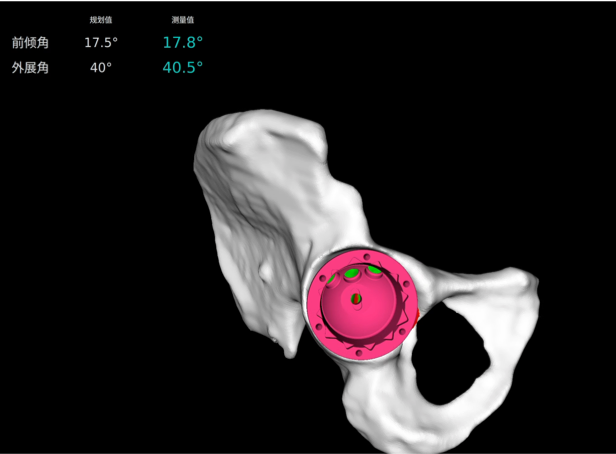

· 個(gè)性化規(guī)劃假體尺寸及安裝角度,預(yù)估安裝效果。

· 融合 CT 和 3D 模型,直觀顯示假體植入效果。

· 精準(zhǔn)高效執(zhí)行手術(shù)操作,實(shí)時(shí)安裝角度顯示,誤差控制在1°以?xún)?nèi)。